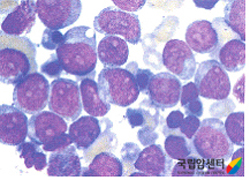

현미경으로 본 골수세포

2009.08.20